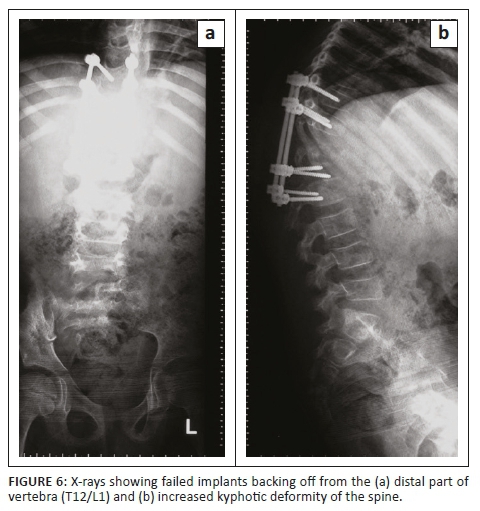

X-rays showed failed implants; therefore, the pedicular screws were backed off from the distal part of the vertebra (T12/L1) with increased kyphotic deformity of the spine (Figure 6).

The majority of spinal tuberculosis cases can be managed non-surgically. Radical surgery at a younger age, combined with anti-tuberculosis treatment, has been associated with favourable patient outcomes.15 The surgical procedures can be done anteriorly or posteriorly with instrumentation. Other studies have reported that about 0.7% of patients can have implant failure following a spinal tuberculosis operation.12 In this study, surgery was performed and anti-tuberculosis treatment was given. The patient fully recovered after 15 months.